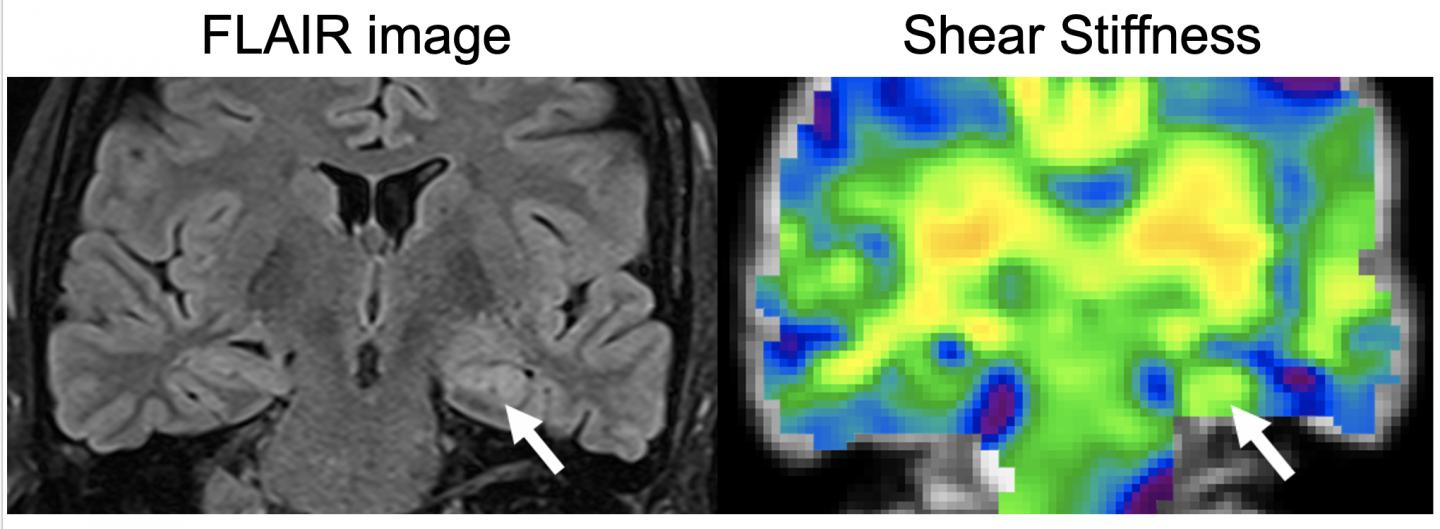

image: A FLAIR image, left, is conventionally used to show what part of the brain is impacted by the disease, is shown with the corresponding MRE stiffness map from the patient showing stiffness changes due to disease. The affected side is indicated by the arrow.

A new study uses magnetic resonance elastography to compare the stiffness of the hippocampus in patients who have epilepsy with healthy individuals. The technique can improve the detection and characterization of the disease.

Mesial temporal lobe epilepsy is the most common form of epilepsy that is resistant to medication. Unfortunately, current detection methods, which include magnetic resonance imaging, can only visualize the epilepsy-induced changes in the brain after significant damage has occurred.

The researchers used MRE to see if there were any changes in the hippocampus. "The hippocampus is the part of the brain that is involved in memory," said Brad Sutton, a professor of bioengineering and the technical director of Beckman's Biomedical Imaging Center. "In the early stages of epilepsy, there is a little bit of damage to the structure, which we can detect with MRE."